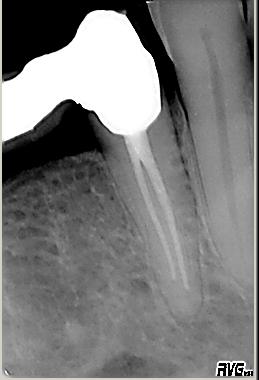

Kontrollaufnahme

Kontrollaufnahme im November 2002. Wurzelfüllung in lateraler Kondensation mit genormter Guttapercha und AH 26